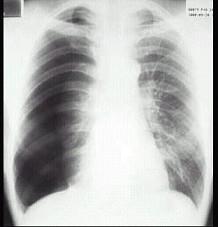

男性,34岁,突感胸部不适,X线检查如图最可能的诊断是 ( )A.肺部炎症B.胸腔积液C.肺结核D.正常心、肺、膈E.气胸

问题 男性,34岁,突感胸部不适,X线检查如图最可能的诊断是 ( )

选项 A.肺部炎症 B.胸腔积液 C.肺结核 D.正常心、肺、膈 E.气胸

答案 E